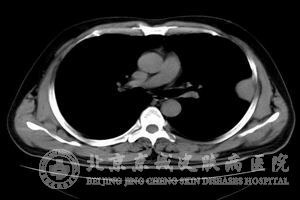

其次,对患者进行椎管造影、CT以及MRI检查可以发现患者有中枢神经肿瘤;